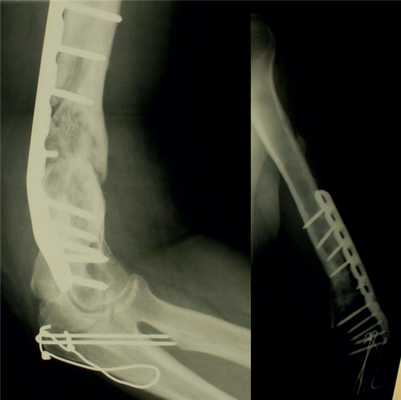

Консолидация перелома при кровоснабжаемой костной пластике была достигнута в 36 (88%) случаях в течение 4-6 мес (рис. 2): Рис. 2. Результаты оперативного лечения с использованием кровоснабжаемой костной пластикой. в группе применения малоберцового трансплантата консолидация была достигнута в 33 случаях, в группе трансплантата из мыщелка бедренной кости — в 3 случаях.